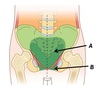

Name structures A, B and C

A - Caecum

B - Mesoappendix

C - Appendix